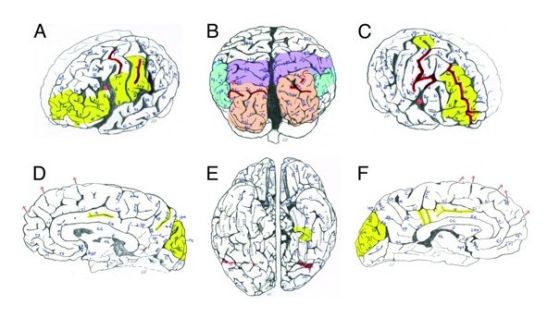

在过去的数十年间,科学家们仅仅发表了6篇通过同行评议的基于这些散落各处的样本材料撰写的论文。在这些研究中有些确实发现了爱因斯坦大脑中一些有趣的特征,包括发现在爱因斯坦大脑的一些部分拥有更高密度的神经分布,以及更高比例的神经胶质,这些物质是负责传递神经脉冲信号的。两篇基于大脑整体解剖学研究的论文,其中包括一篇由人类学家,佛罗里达州立大学的迪恩·福柯(Dean Falk)发表于2009年的文章,它们均指出爱因斯坦的大脑顶叶拥有非常独特的沟回和褶皱,这一部分的独特构造可能与爱因斯坦惊人的物理思维能力有关。

研究小组将爱因斯坦的大脑与85位其它人士的大脑进行了对比,结果发现这位伟大物理学家的大脑的确存在一些不同寻常之处。尽管爱因斯坦的大脑尺寸并不突出,然而其大脑某些区域的沟回和褶皱结构的发育的确存在不同寻常之处。举例来说,在其大脑左侧区域负责控制将感觉信息输入面部和舌头运动控制中枢的部分面积要比一般人大得多;而他的前额皮质,即与人的计划,注意力和坚忍特性相关的区域同样要比常人发达。

福柯表示:“在每一个脑叶部分,包括额叶,顶叶和枕叶部分,都观察到了拥有异乎寻常的复杂沟回的区域。”至于在研究中所观察到的和脸部和舌头运动相关区域的异常发达,福柯认为这可能与爱因斯坦广为人知的一种说法有关,据说爱因斯坦在思考过程中似乎“肌肉的运动”要多过“言词的使用”。

尽管这种说法一般被解读为爱因斯坦在思考有关宇宙的理论时站在一种非常客观的立场之上,但是福柯表示:“这也可能和爱因斯坦能够以不同寻常的方式使用其运动皮层有关。”这种能力可能和他所具有的抽象思维能力有关。